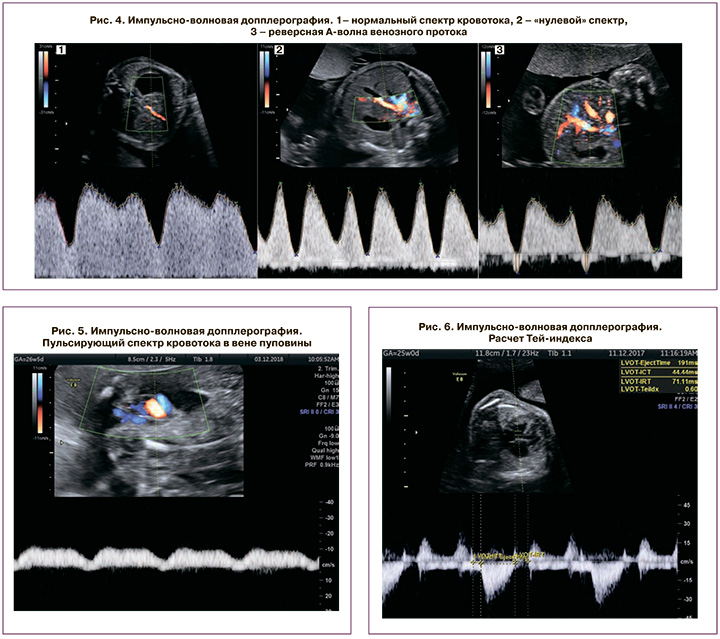

Для оценки сердечно-сосудистой системы плодов проводится эхокардиография (Эхо-КГ), которая позволяет диагностировать морфологические и функциональные изменения. При Эхо-КГ осуществляется исследование четырехкамерного среза сердца, срезов через выходные тракты левого и правого желудочков, проекции трех сосудов и трахеи, а также оценивается венозная гемодинамика [4, 5]. Наибольшее внимание исследователей при допплеровской оценке венозной гемодинамики плода в последние годы привлекает изучение кровотока в венозном протоке. При перегрузке правых отделов сердца визуализируется аномальный кровоток в венозном протоке – нулевые и реверсные значения в фазу сокращения предсердий.

Показатель производительности миокарда, также известный как индекс Тэя, является единицей измерения глобальной систолической и диастолической функции миокарда. В нескольких исследованиях было продемонстрировано, что Тэй-индекс коррелирует со степенью дисфункции миокарда даже при ранних стадиях ФФТС [6].

Измерение размеров сердца, расчет кардио-торакального индекса, толщины миокарда желудочков и межжелудочковой перегородки и определение регургитации на атриовентрикулярных клапанах, индекс Тэя, отношение E/A, доказанная обструкция выносящего тракта правого желудочка могут использоваться для оценки прогрессирования ФФТС.

Венозный проток оценивался на поперечном или сагиттальном срезе брюшной полости плода с помощью цветного допплеровского картирования. При перегрузке правых отделов сердца регистрируются аномальный кровоток в венозном протоке – его снижение (повышение пульсационного индекса более 95 перцентили), а впоследствии – появление нулевого и реверсного типа кривой. Оценка кривой классифицировалась как нормальная при положительной А-волне или аномальная – при отсутствующей или отрицательной А-волне (рис. 4). Также при прогрессировании кардиомиопатии определяется пульсирующий спектр кровотока в вене пуповины (рис. 5); функция миокарда.

Для оценки функции миокарда использовался индекс производительности миокарда, или Тей-индекс (рис. 6). Увеличение Тей-индекса более 0,35±0,05 считалось признаком кардиомиопатии; выявление врожденных пороков сердца, возникающих вследствие ФФТС (рис. 7).

Диагностическими критериями кардиомиопатии плода и новорожденного являлись такие изменения сердечно-сосудистой системы, как гипертрофия миокарда, кардиомегалия, недостаточность атриовентрикулярных клапанов, венозной гемодинамики (нулевая или реверсная А-волна венозного протока, пульсация вены пуповины), производительности миокарда (Тей-индекс более 0,33) и наличие обструкции выносящего тракта правого желудочка.